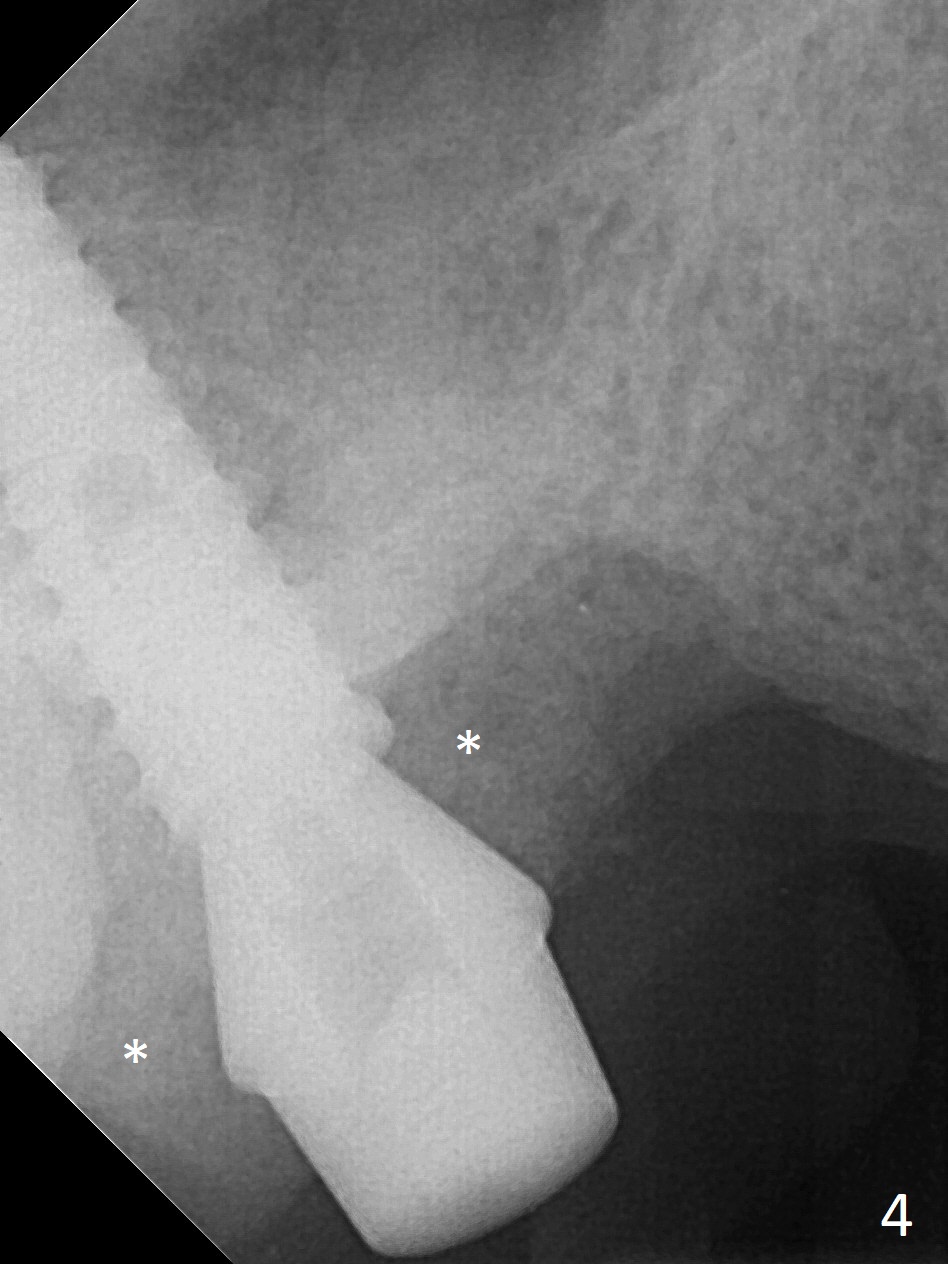

It is difficult to use hard tissue landmark (drill stopper) to make osteotomy in the fresh extraction socket because of socket irregularity and hemorrhage. Once osteotomy is initiated, depth is more reliably controlled with soft tissue landmark (such as gingival margin). This happens in today's case. Without CT information, the osteotomy is established in the buccal slope of the septum of the tooth #2 (after extraction) by using alternatively Magic Sinus Lifter and 4.8 mm Magic Drill (MD). Finally the sinus floor (Fig.1 red dashed line) is lifted after the MD reaches ~16 mm counting from the gingival margin, consistent with preop panoramic X-ray and intraop PA measurement. The 4.5x11 mm dummy implant is close to the impacted 3rd molar (1). Following use of Lindamann bur to move the osteotomy mesially, a 5x9 mm dummy implant is placed away from the 3rd molar (Fig.2 (3: residual root of the 1st molar)). The latter is intentionally not removed in order to maintain osteotomy integrity. A 5x13 mm IBS implant is placed with >50 Ncm; a 6.5x4(4) mm abutment is hand tightened (Fig.3). The remaining large socket is filled with Vera Graft (Fig.4 *). Two months postop, the abutment changes to 6.5x5.7(2) mm without provisional (Fig.5). Nearly 3 months postop, the patient will return for #3 residual root extraction and implant placement with incision (Fig.6). Osteotomy will be initiated in a slope. Prepare surgical round bur for flattening. After placement of a healing abutment, periodontal dressing is to be applied. Take photos to show gingival adaptation to the new abutment without implant exposure at #2.